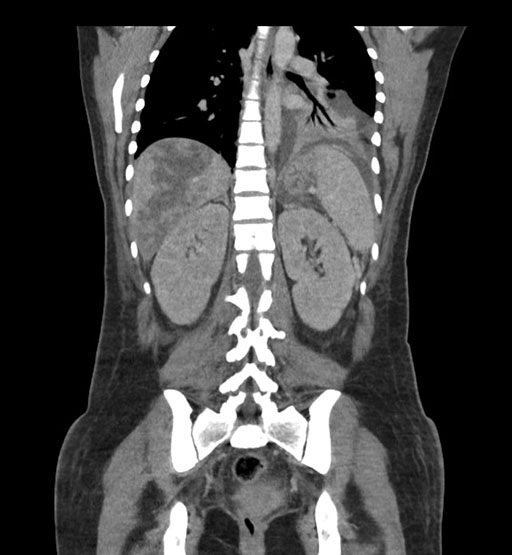

Coronal Arterial

Coronal Venous